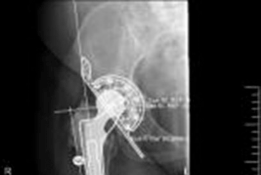

Meticulous preoperative planning is the cornerstone of successful cup-cage reconstruction. Standard radiography must include an anteroposterior pelvis view, an anteroposterior view of the affected hip, and Judet oblique views (iliac and obturator) to assess the integrity of the anterior and posterior columns. The presence of a pelvic discontinuity is often suggested by a visible fracture line through the acetabulum, medial translation of the inferior hemipelvis, or a break in the Kohler line.

A highly porous metal cup is then impacted into the defect. The cup is often placed in an off-axis orientation, prioritizing host bone contact and initial stability over anatomic version and inclination. The subsequent cementation of the liner into the cage will correct the final articular geometry. If large cavitary defects remain behind the cup, highly porous metal augments or impacted cancellous allograft are utilized to fill the voids and support the primary shell. Multiple multi-hole screws are placed through the cup into the superior dome and posterior column to maximize initial fixation.

Cage Contouring and Fixation

The appropriate cage is selected based on preoperative templating and intraoperative trialing. The inferior flange is contoured to fit into the prepared ischial slot. The superior flange is contoured to lie flush against the lateral aspect of the ilium. Proper contouring is critical; a poorly contoured cage will experience high bending moments and subsequent fatigue failure.

The cage is inserted by first seating the inferior flange into the ischium. The superior flange is then impacted against the ilium. The cage should sit intimately against the previously placed highly porous cup. Fixation begins with the placement of cortical or cancellous screws through the superior flange into the dense bone of the ilium, aiming toward the sacroiliac joint. Screws are also placed through the central dome of the cage, passing through the cage, the underlying porous cup, and into the host bone, effectively locking the two components together. Care must be taken to avoid the superior gluteal neurovascular bundle during superior flange screw placement and the external iliac vessels during anterior screw placement.

Liner Cementation and Final Reduction

Once the cage is rigidly fixed, the surgical site is thoroughly irrigated and dried. A highly cross-linked polyethylene liner is selected. The back of the liner is often scored to enhance cement interdigitation. High-viscosity polymethylmethacrylate bone cement is applied to the inner surface of the cage.

The liner is pressurized into the cement mantle. The critical advantage of this technique is that the surgeon can manipulate the version and inclination of the polyethylene liner independently of the orientation of the underlying cage and cup. The liner is held in optimal anatomic orientation (typically 15 to 20 degrees of anteversion and 40 to 45 degrees of inclination) until the cement fully cures. Excess cement is meticulously removed to prevent third-body wear. The femoral component is then reconstructed as dictated by the femoral defect, and the hip is reduced and assessed for stability through a full range of motion.